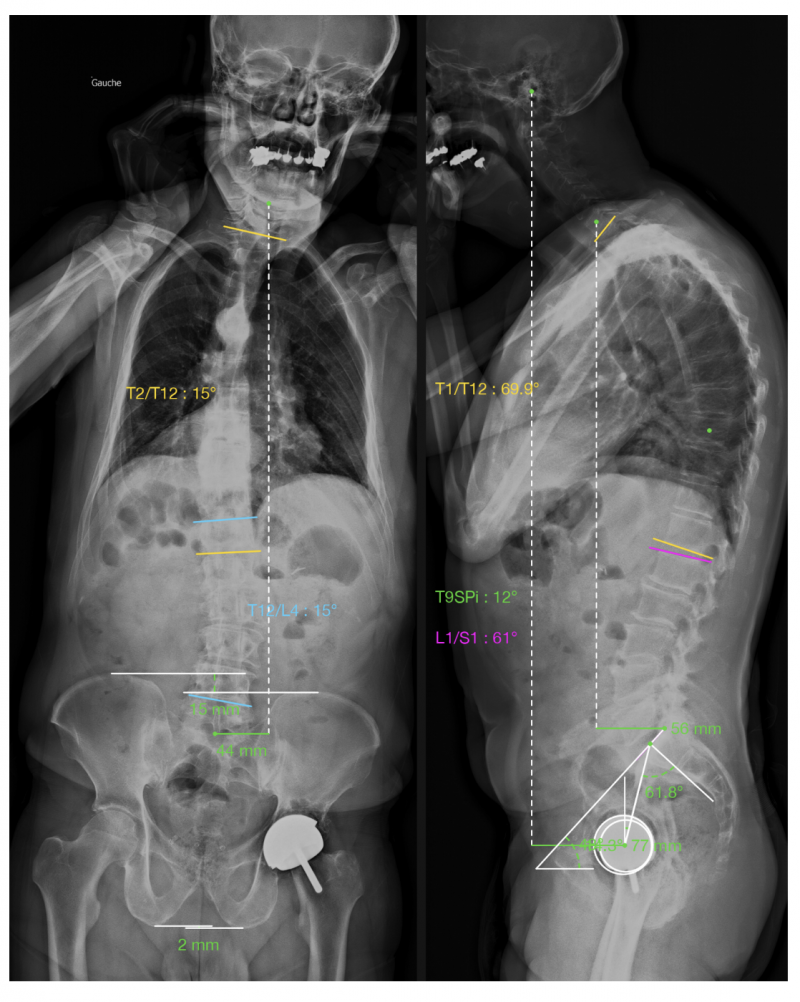

Figure 5: Exemple d’analyse globale d’un déséquilibre rachidien coronal et sagittal de l’adulte

Une séquence habituelle de décompensation sagittale est la perte de la lordose lombaire en rapport avec l’arthrose (IP-LL), s’accompagnant ensuite de compensations: d’abord une extension au niveau thoracolombaire (la colonne thoracique devient plus plate par diminution de la cyphose), puis par une rétroversion du bassin (équivalent à une extension de hanche) puis une flexion des genoux. Au niveau cervical, l’objectif est de maintenir un regard horizontal, par augmentation de la lordose cervicale. L’intérêt de l’EOS est de quantifier ces phénomènes en position debout, donc dans des conditions fonctionnelles. Dans le cadre des chirurgies de ré-équilibrage sagittal, la mesure préopératoire de ces paramètres permet d’anticiper le degré de correction nécessaire et d’évaluer le résultat post-opératoire avec une bonne reproductibilité.

Au-delà du rachis, l’EOS a trouvé sa place dans l’analyse du bassin et des membres inférieurs. L’examen en charge révèle les interactions entre la morphologie pelvienne, les axes mécaniques des fémurs et des tibias, et la répartition du poids corporel. On peut mesurer les angles de varus ou de valgus, les torsions fémorales et tibiales et surtout les inégalités de longueur des membres. Une différence de 10 mm ou plus est généralement considérée comme cliniquement significative : elle peut s’associée à une bascule pelvienne voir une scoliose compensatrice.

En-dessous de cette valeur, les compensations musculaires suffisent la plupart du temps ; au-delà, une correction par semelle peut être indiquée, et lorsque l’écart dépasse deux centimètres, la discussion chirurgicale peut se poser.